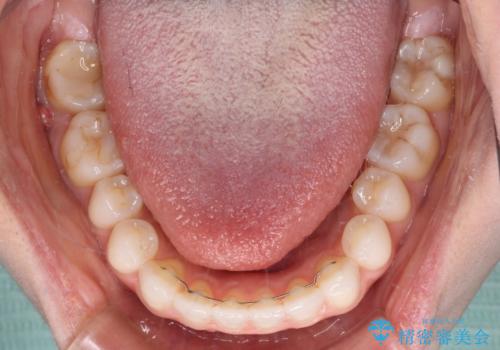

上下前歯が接触しない オープンバイトをインビザラインで改善

- インビザライン

- 10ヶ月

上下の奥歯を圧下させるようにすることで、前歯を接触させるように計画しました。

上下の隙間に舌が入り込むことがオープンバイトの原因であったため、舌の筋肉のトレーニングも並行して行い、後戻りの抑制を図りました。